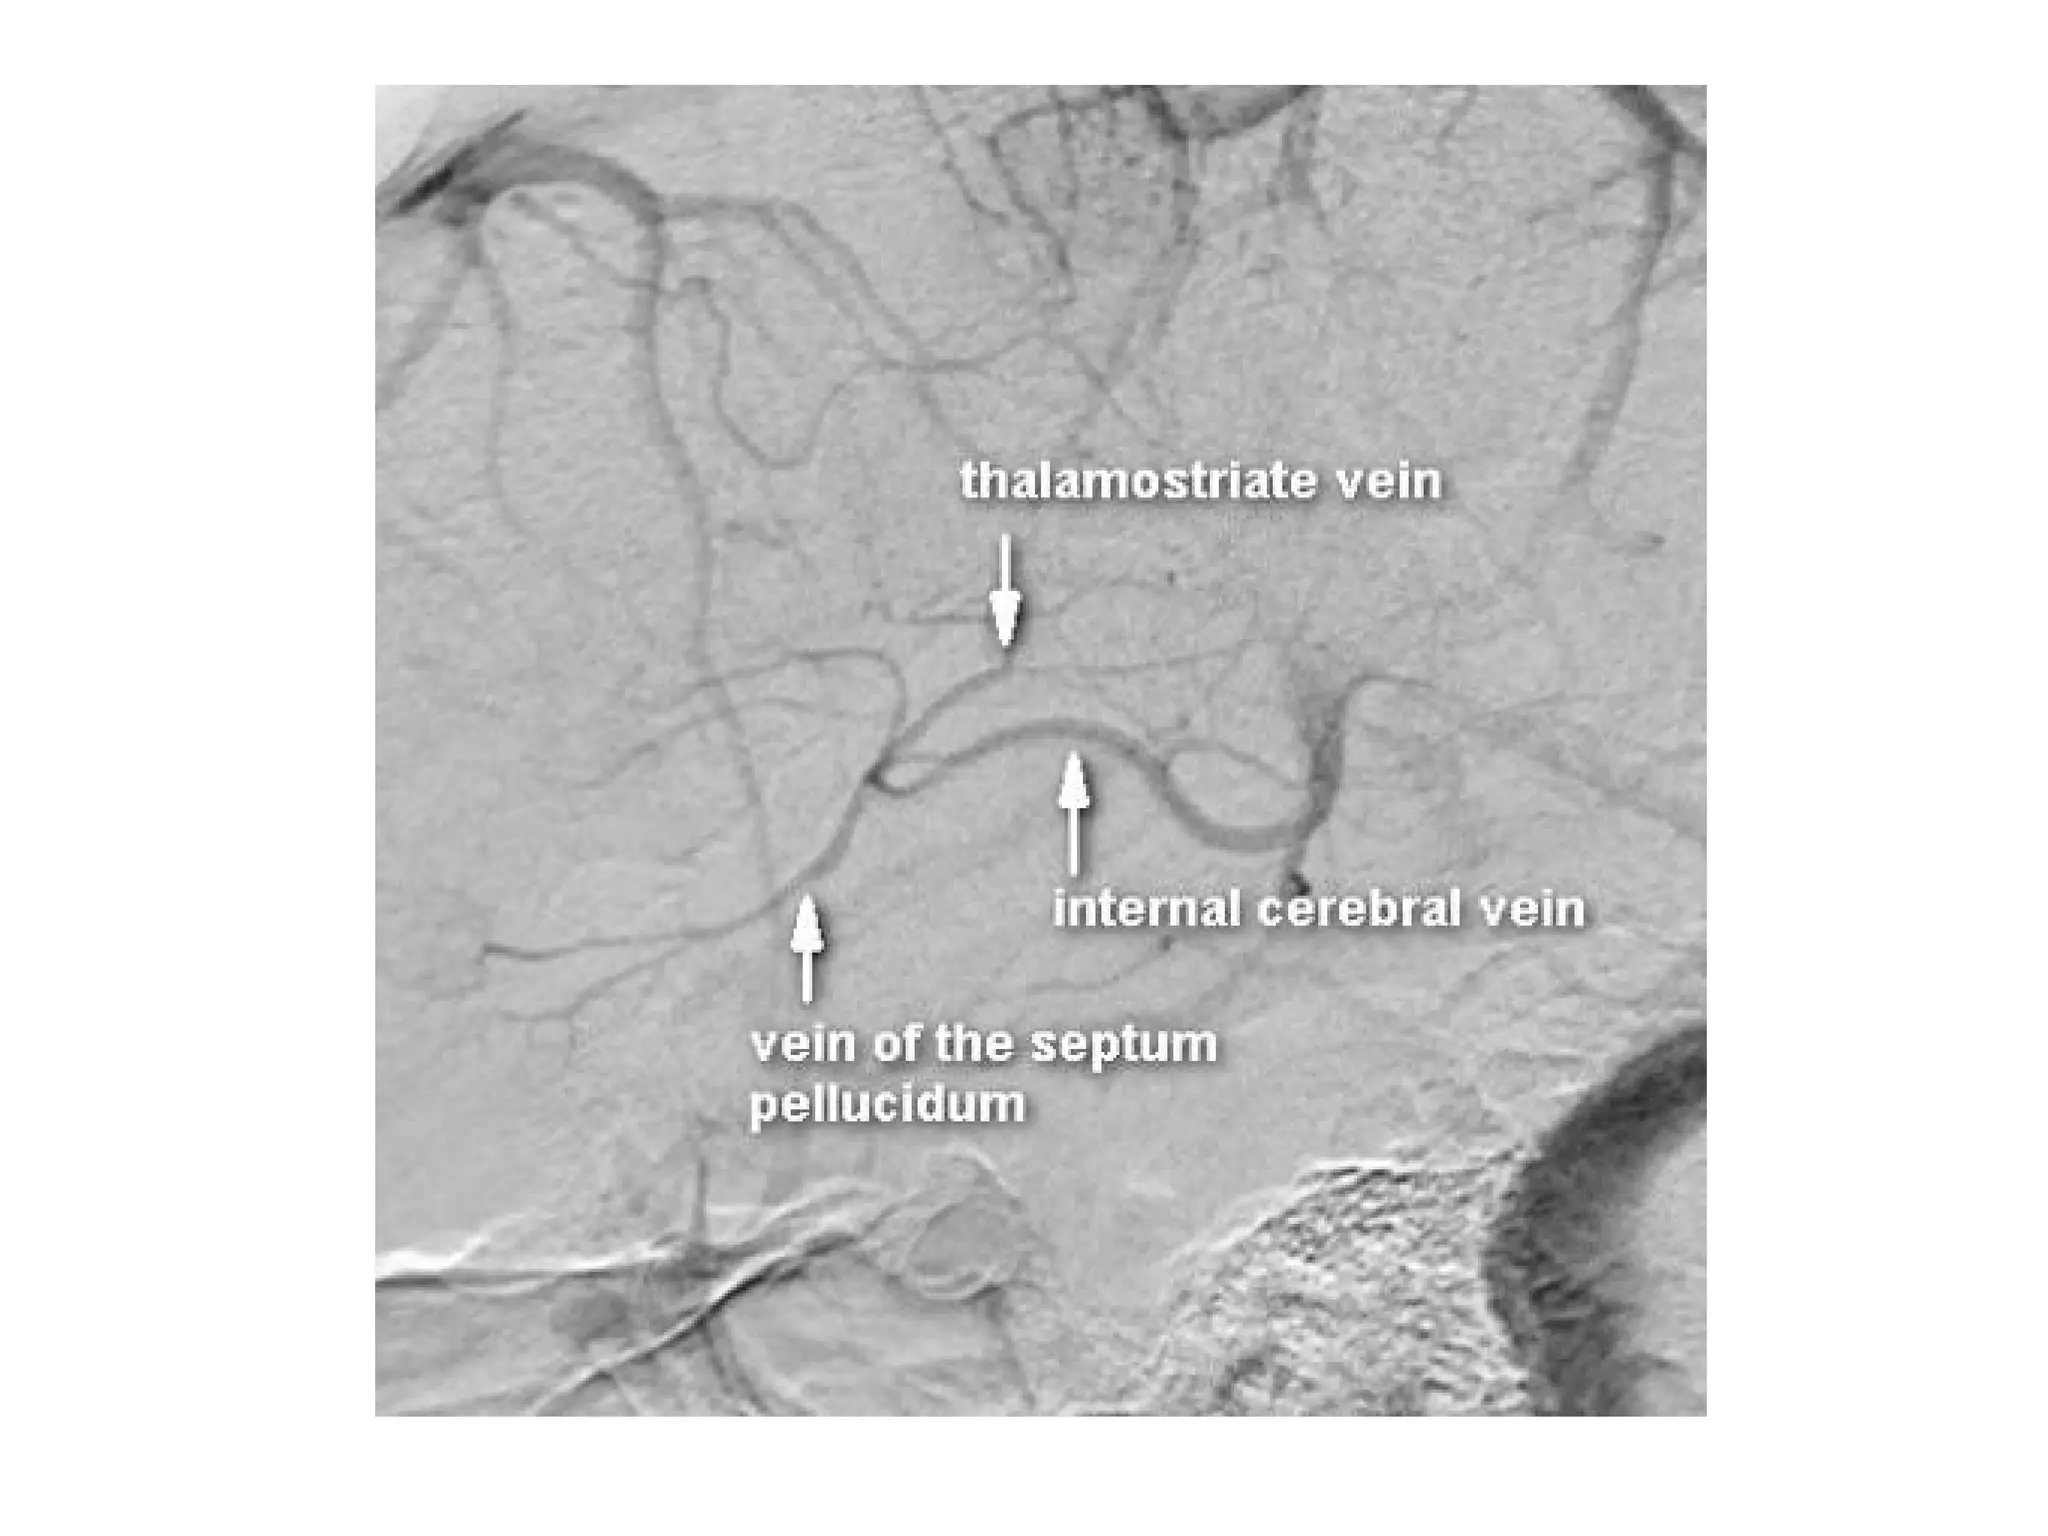

b) Deep Cerebral Veins :

-Consist of paired internal cerebral veins , the

basal vein of Rosenthal & the vein of Galen

-The venous angle is the intersection of the

septal vein & the thalamostriate veins , the

venous angle is the angiographic mark for the

foramen of Monro